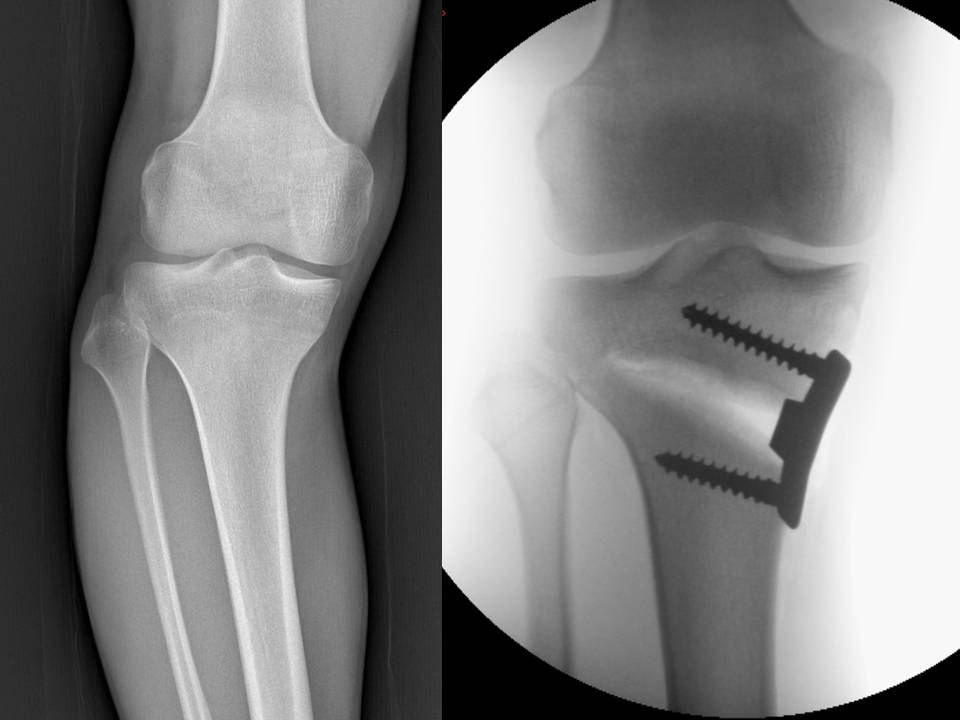

fig 6 C-D